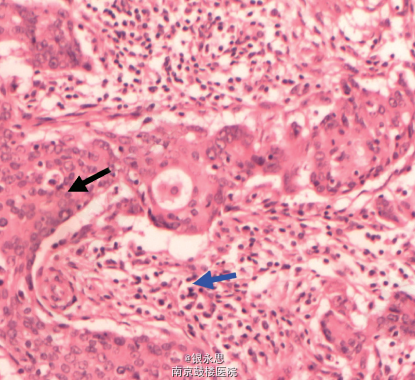

在全身麻醉下行左乳腺单纯切除术+前哨淋巴结活检术,术中快速病理证实前哨淋巴结出现转移,遂改行左侧乳腺癌改良根治术。 术后病理报告:左侧乳腺交界性叶状肿瘤,伴上皮癌变。免疫组织化学: ER ( -) 、PR( -) , HER- 2( -) ,Ki67( +30% ) ,CK5 / 6( +) ,波形蛋白( Vimentin) ( +) ,CK ( +)。 术后给予 6 疗程 TAC( 多西他赛+吡柔比星+环磷酰胺) 方案化疗、1 疗程放射治疗。